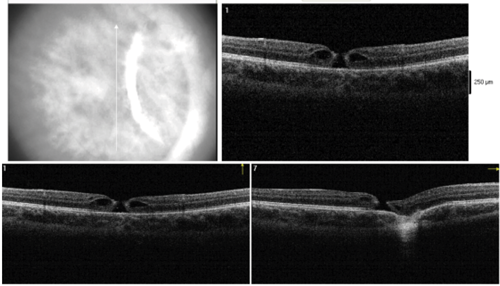

Figure 3: Optical coherence tomography at one month (Top) and three months (Bottom)

after the trauma showing progressive full thickness traumatic macular hole.

The visual prognosis of choroidal rupture has long been thought to be poor when the fovea is involved, with a possible late complication of choroidal neovascularisation. As can be seen from the OCT (Figures 3a and b), the fovea is indeed involved in our patient, still her visual acuity improved remarkably before the macular hole developed. This was first observed by another consultant in my deanery, Mr Raman, who found in a series of 32 eyes that foveal choroidal ruptures may indeed regain good central vision over a longer follow-up period and that multiple choroidal ruptures do not necessarily predict a poor visual outcome [3].